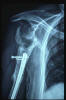

Fractura impactada de húmero .